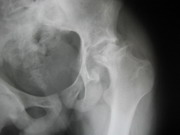

TRAUMA

Besides routine trauma, we specialize in advanced traumatology. We manage all the pelvic and acetabular fractures and spinal fractures with neurological deficit, with equal case.